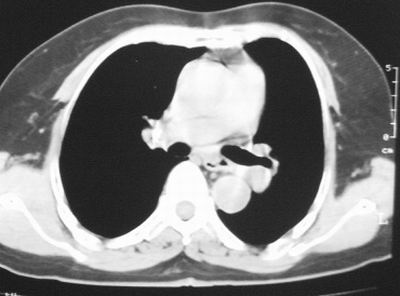

患者,女,64岁,4年前左腮腺"多形性"腺瘤手术治疗史.现复查胸部ct见左下肺块状影,该影与原左腮腺手术是否有联系?

本次复查胸部ct

左下肺癌伴左肺门淋巴结转移

左下肺软组织块影,有分叶、毛刺、空泡及胸膜牵拉征,左下肺周围性肺癌。

支持考虑左下肺原发性肺癌,并左肺门淋巴结肿大

左下周围型肺癌伴左肺门淋巴结及右肺转移可能性大.

左肺下叶周围型肺癌,支持!(软组织肿块+分叶+毛刺+空泡+胸膜凹陷征)

左下肺后基底段实性肿块,周围有毛刺,病变周围有肺气肿,与降主动脉间有条带状影相连,病灶4年前查体发现,纵隔内未见肿大淋巴结。考虑.肺隔离症,建议增强扫描与周围型肺癌鉴别。